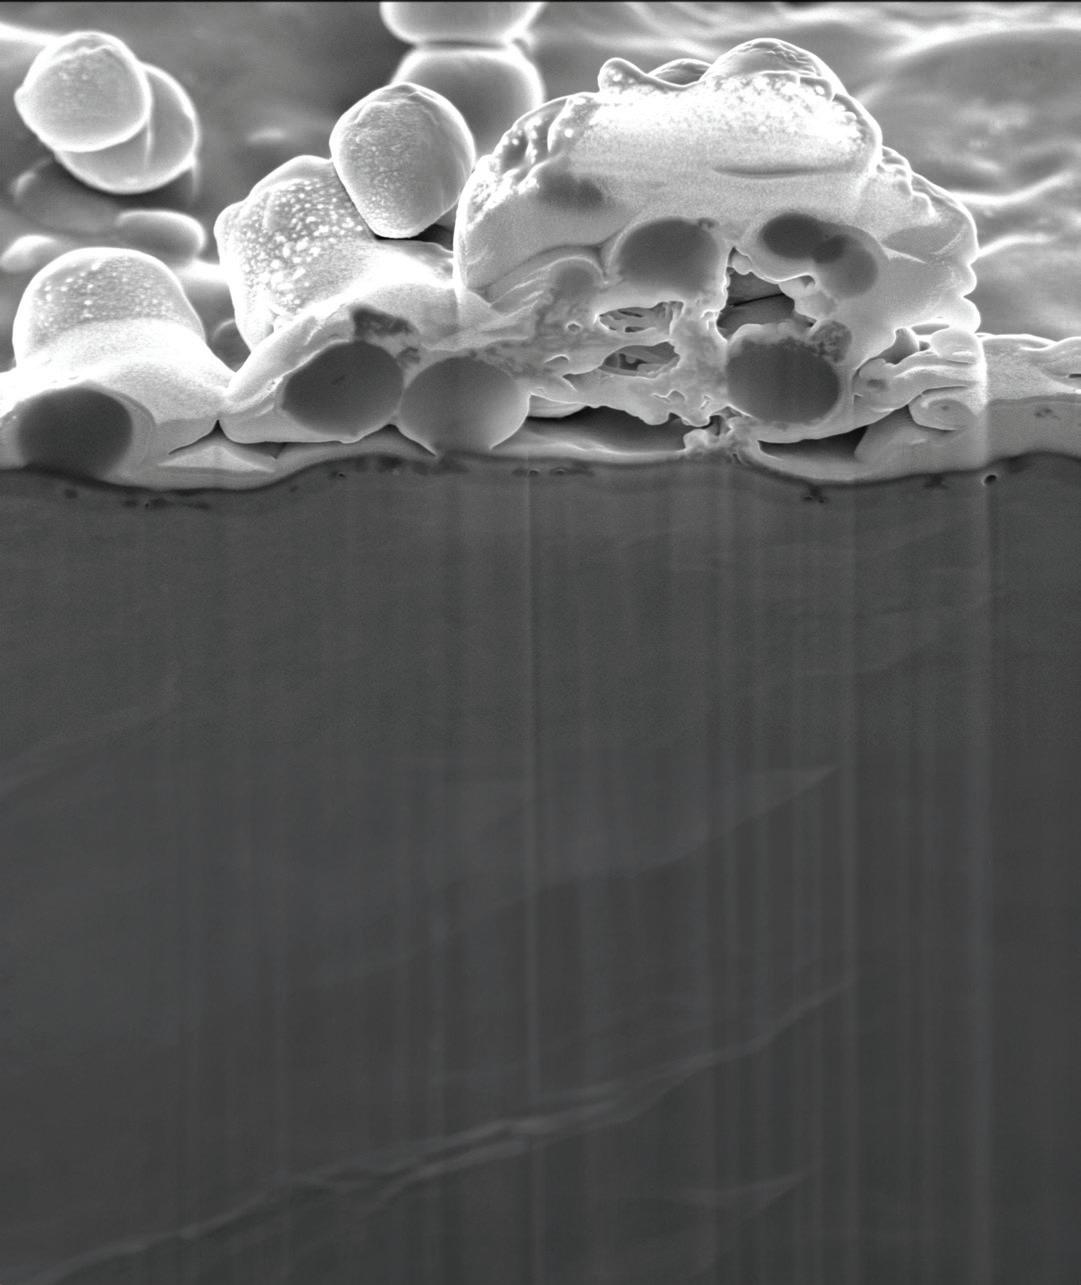

This scanning electron microscope image shows Orthobond’s Ostaguard antimicrobial coating killing methicillin-sensitive Staphylococcus aureus (MSSA) bacteria.

Image courtesy of Orthobond

The resulting layer of positively charged, quaternary ammonium molecules on an implant’s surface measures only one-millionth of an inch and immobilizes, perforates and destablizes microbes.

“It’s like flypaper because bacteria is negatively charged and our surface is positively charged,” Nichols said. “It actually draws them to our surface, puts little pin pricks in the bacteria and starts the death process. As they try to move around, it breaks them apart and kills them.”

Because the technology neutralizes microbes mechanically, it even works on antibiotic-resistant bacteria like the Mu50 strain of methicillin-resistant Staphylococcus aureus (MRSA), which has evolved efflux pumps to remove antibiotics from its cells and render them ineffective.

The Ostaguard antimicrobial coating kills common infection-causing microbes such as Staphylococcus aureus, Pseudomonas aeruginosa, E. coli, methicillin-resistant Staphylococcus aureus (MRSA), E. cloacae and C. acnes.